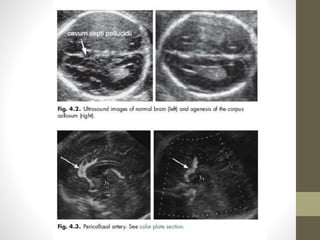

AGENESIS OF CORPUS CALLOSUM

(ACC)

โ€ข The normal development of the corpus callosum begins anterior

(genu) and progresses to posterior (splenium). Agenesis may be

partial (affects dysgenesis posterior aspects) or complete.

โ€ข US Features

โ€ข The corpus callosum is not visible in complete agenesis.

โ€ข โ€ข Colpocephaly

โ€ข โ€ข Lateral ventricles are displaced laterally (parallel lateral ventricles).

โ€ข โ€ข Enlarged 3rd ventricle expands superiorly (high riding third

ventricle).

โ€ข โ€ข Angulated frontal horns (coronal view)( U or VIKING HORN

CONFIGURATION)

โ€ข โ€ข Abnormal (sunburst) gyral pattern in interhemispheric fissure is a

late feature.

โ€ข โ€ข The presence of a cavum septum pellucidum excludes complete

Agenesis